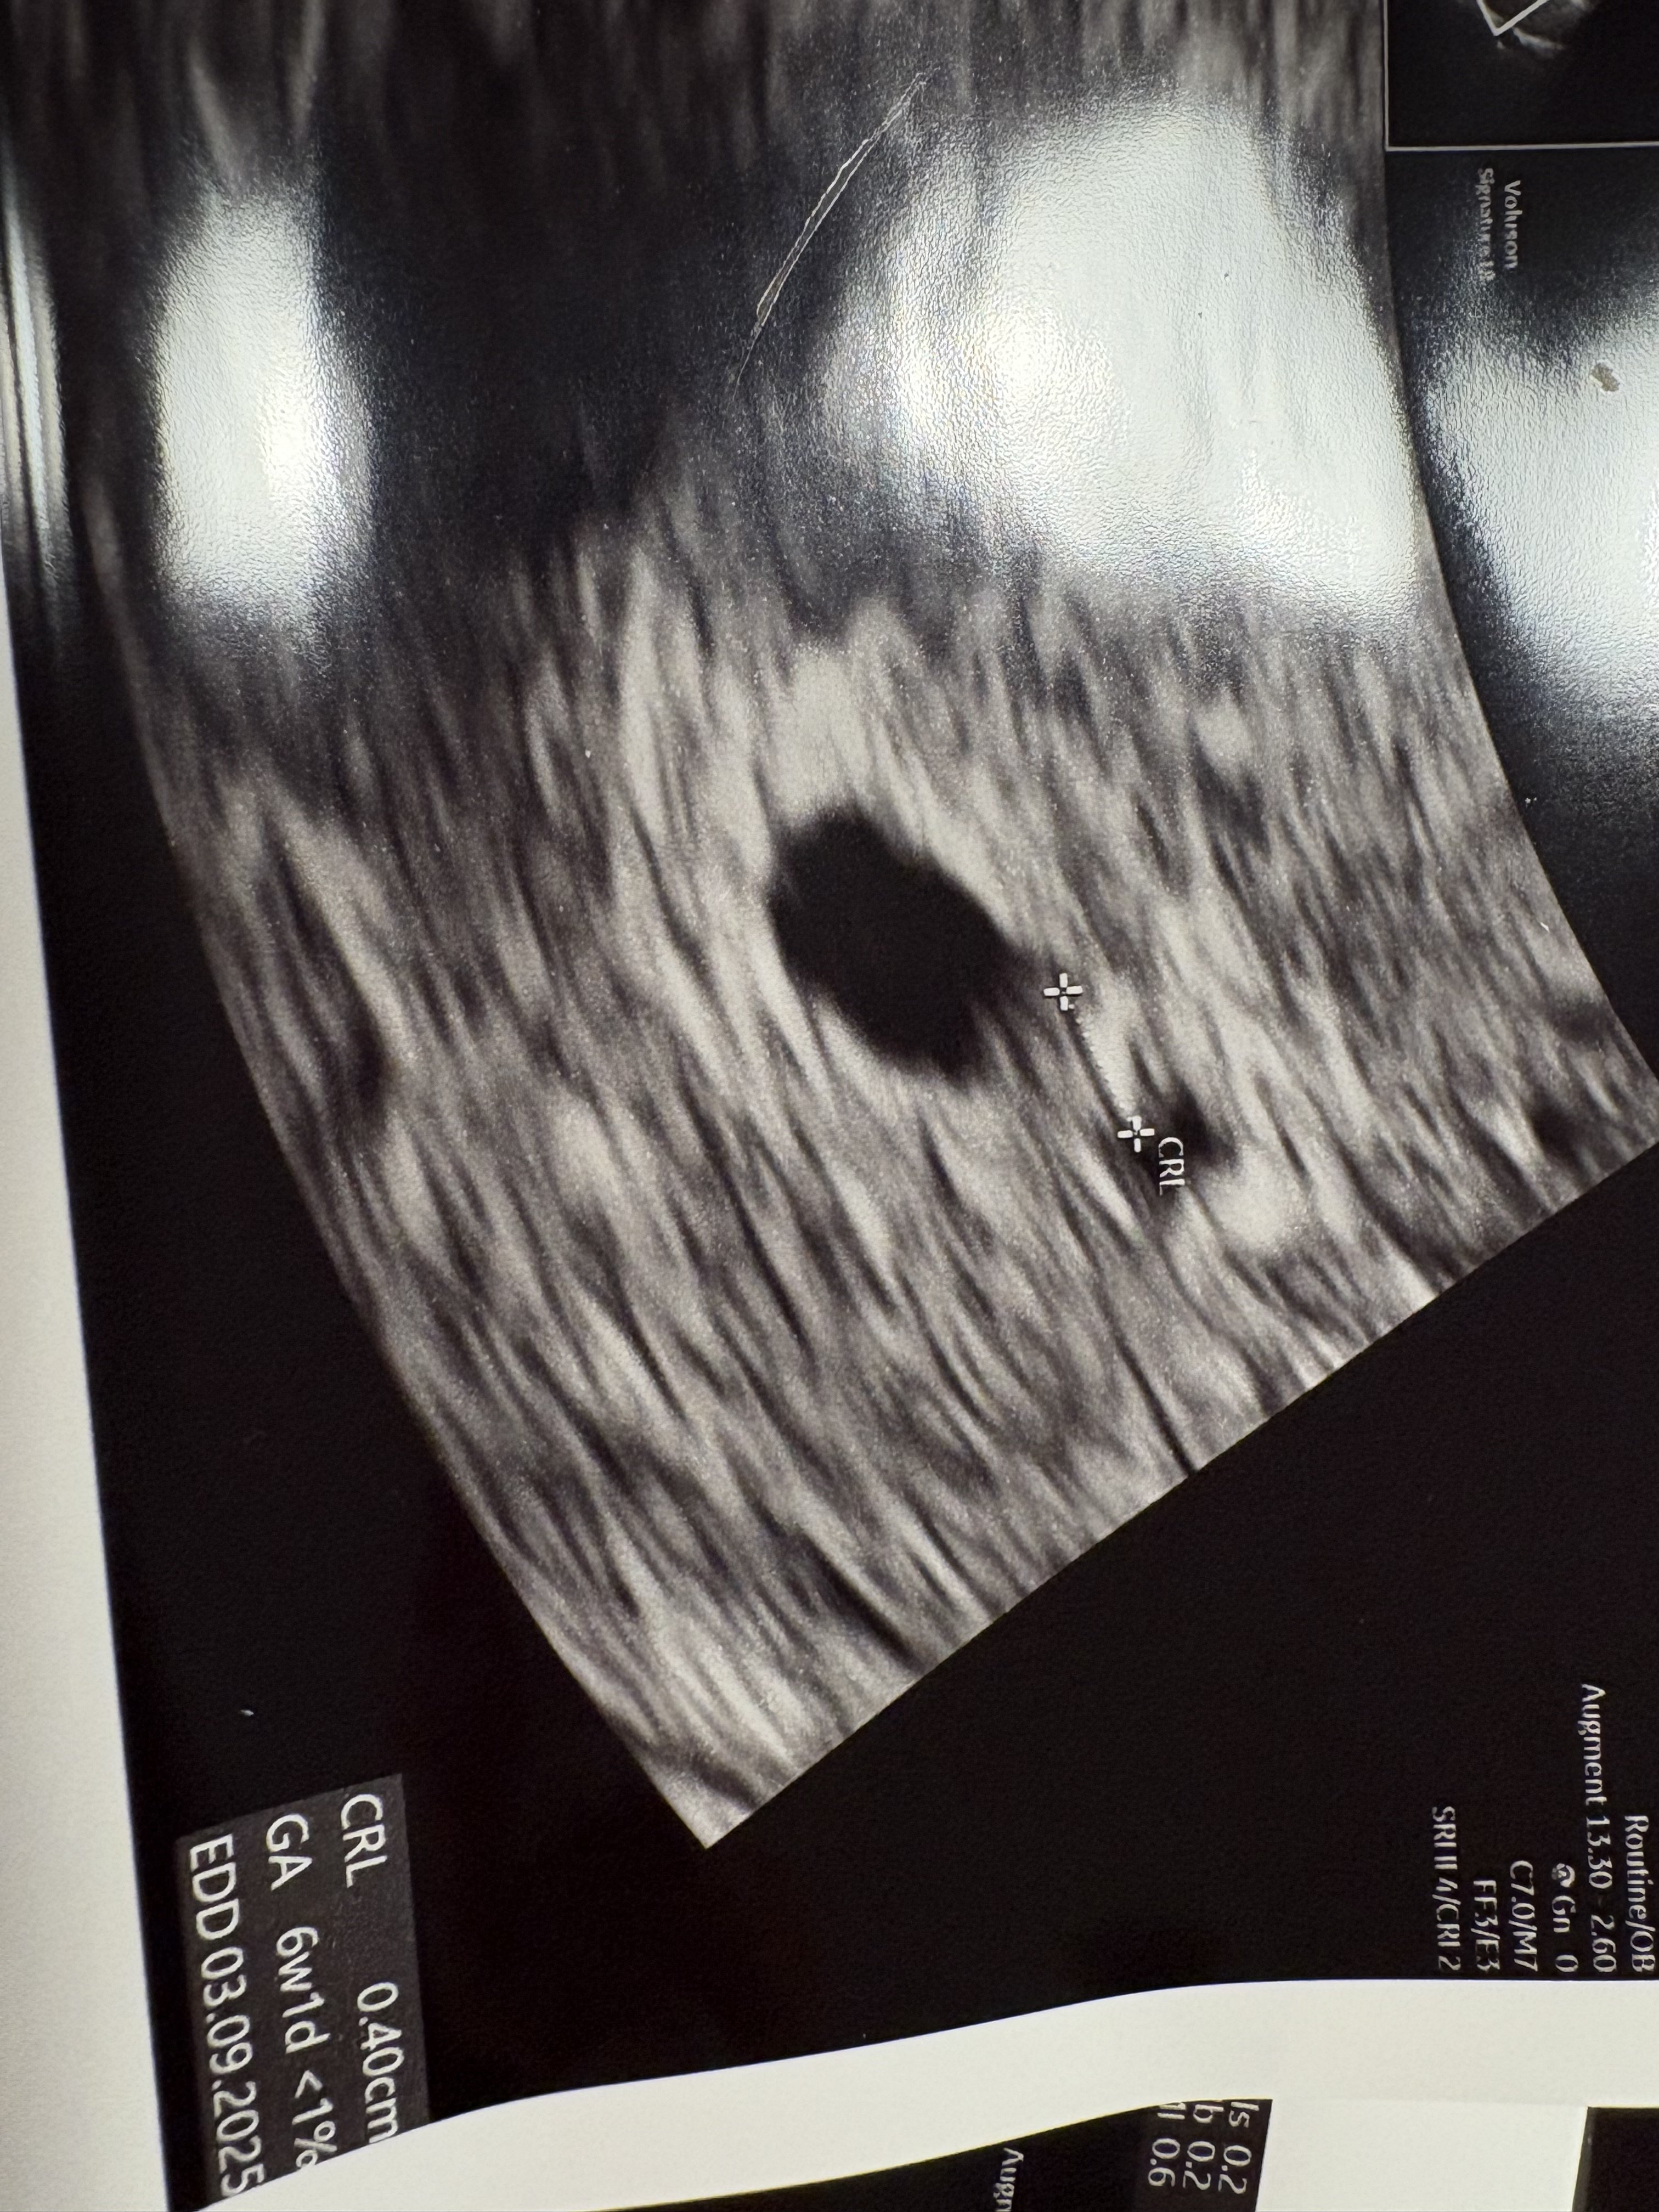

Właśnie siedzę na poczekalni i jest opóźnienie 🤦‍♀️ jeszcze dwie osoby przede mną a ja cała drżę ze stresu, czy wszystko jest ok. Liczę na to, że już coś będzie bo 6+2 to już powinno coś być ☺️

O to moje maleństwo :-)

• IMG_6933.jpeg

1,7 MB · Wyświetleń: 143